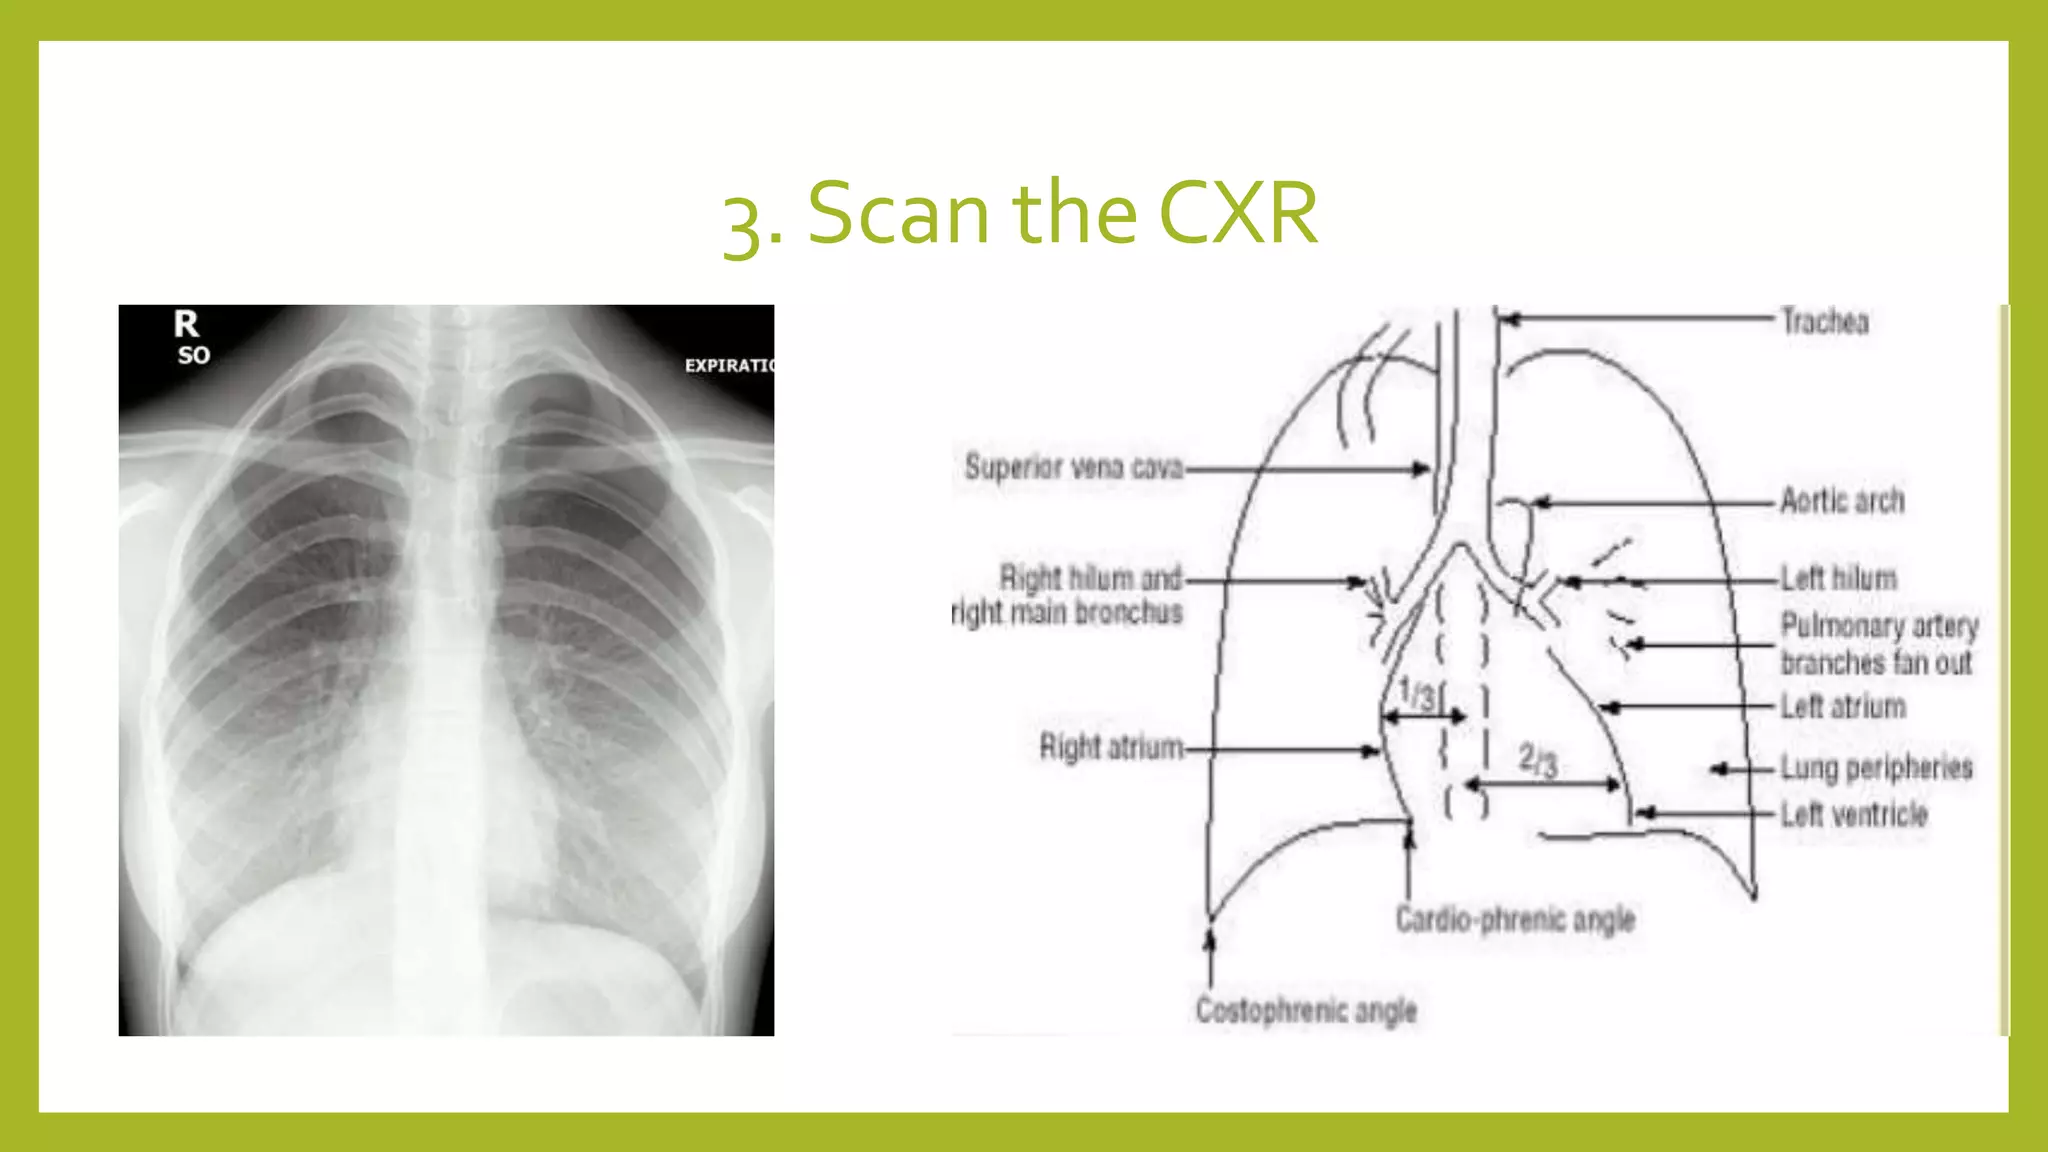

The document provides guidance on approaching and interpreting chest x-rays (CXR). It outlines steps to check the name, date and quality of the film, systematically scan the CXR looking for abnormalities, and determine if the lungs appear too white or black. Specific signs are described to help localize abnormalities, including the cardiac silhouette sign and pleural effusion signs. Examples are given of respiratory distress syndrome, tetralogy of fallot, transposition of great arteries, and total anomalous pulmonary venous return. The take home message is to summarize positive findings, compare to prior CXRs if available, and confirm findings with a radiologist.